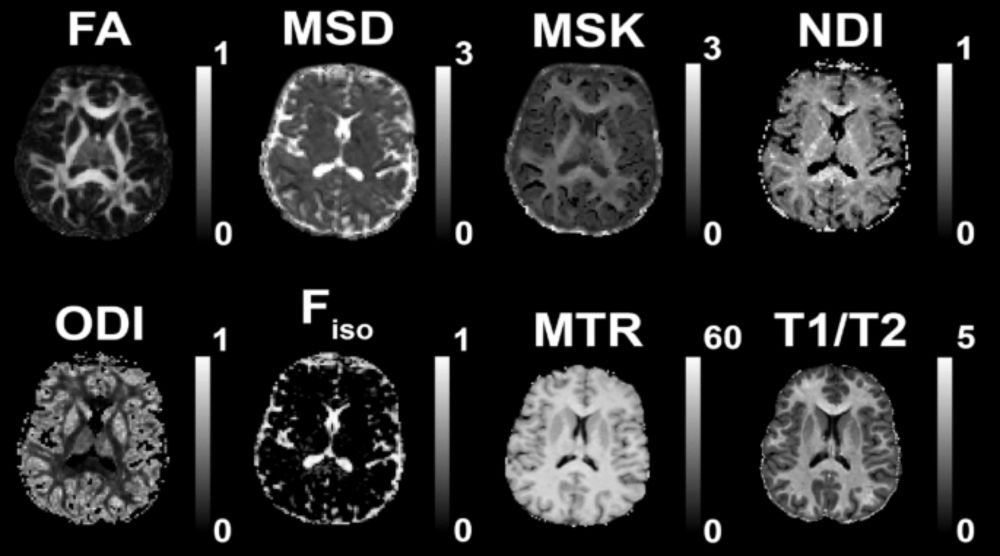

New CamCAN study used 11 different measures to show that white-matter health is multidimensional: 4 latent MRI-derived factors explained 89% of variance, were predicted by vascular health, and predicted cognition